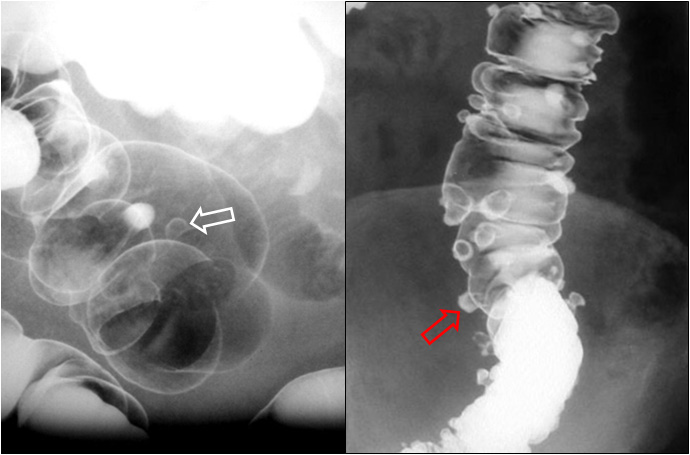

SIGNO DEL SANDWICH

Signo de linfoma abdominal tanto en la TC como en ecografía. Consiste en la presencia de masas adenopáticas que rodean y desplazan la arteria y la vena mesentéricas superiores sin comprimirlas.

La fotografía corresponde a un paciente con linfoma (flecha roja) que forma conglomerados adenopáticos que respetan los vasos mesentéricos (flecha blanca).

Por extensión, se puede emplear este signo en conglomerados linfomatosos que rodean pero respetan otras estructuras vasculares diferentes de los vasos mesentéricos, como vemos en el ejemplo siguiente con las arterias renales.